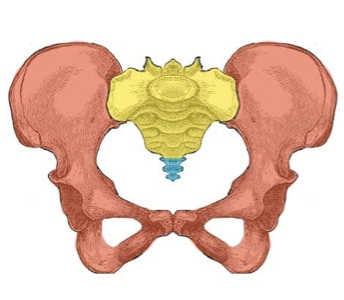

Red?

Hip bones

Yellow?

Sacrum

Blue?

Coccyx

What are the bones of the pelvis?

2 hip bones, sacrum and coccyx